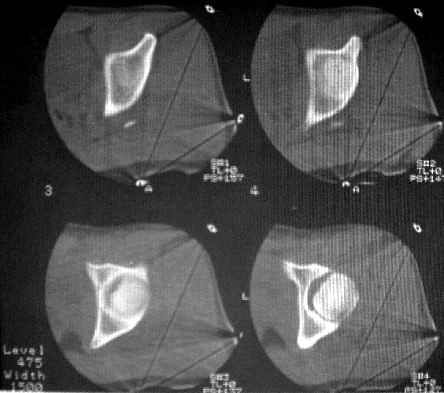

После рентген дообследования складывается мнение об отрыве дистального конца связки головки бедра с костным фрагментом головки (КТ2 скан 3, 4, КТ3 скан 1, прямая проекция - нижнийот 19.05). Данный вариант травмы встречается не часто, но известен, если мне не изменяет память, например см. Мюллер М.Е., Алльговер М., Шнайдер Р., Виллинеггер Х. Руководство по внутреннему остеосинтезу. - Springer-Verlag, 1996. - 750 с. С моей точки зрения, оптимально было бы остеосинтез головки, в обязательном порядке с сохранением целостности связки головки бедра. Как это технически выполнить - вопрос не простой. Кто знает и делал ???

Уважаемые коллеги! Заканчивая обследование больного с переломо-вывихом бедра сделал ему обычные R-томограммы. Кажется удалось "поймать" и отломок и донорское место. Мои выводы - в скиаграмме. Считаю, что это передне-нижний фрагмент головки, образовавшийся вследствии отрывного перелома. На томограммах отломок обозначаю длинной стрелкой, а место откуда он оторвался - более короткой. Учитывая тот факт, что его размеры по КТ 25 х 15 мм считаю, что его фиксация на место необходима для профилактики артроза, что при 16-ти летнем возрасте пациента важно в плане максимального отодвигания эндопротезирования. Планирую оперировать его 24.05.05 г. Результаты представлю.

Несколько соображений к "картинкам". На прямом снимке и КТ-томограммах все типичные линии вертлужной впадины: крыша, передняя стенка, задняя стенка - сохранены. На КТ-сканах 6 и 7 появляется фрагментация головки. С учетом R-томограмм отломок расположен спереди-снизу, а не сзади-сверху от сустава, как написано в описании КТ.